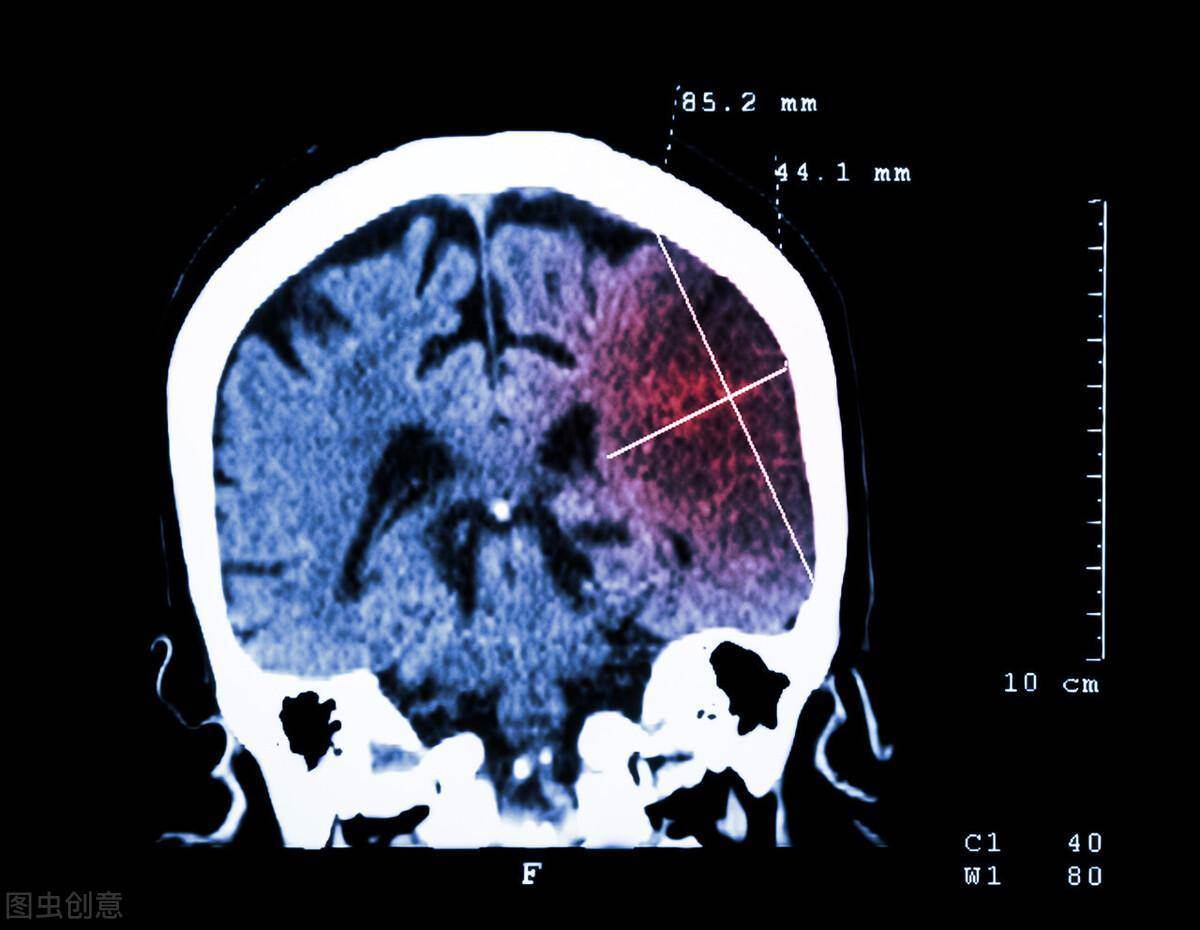

49歲的鄧先生,晨起後突然感到頭暈嘔吐,右側肢體也開始越來越乏力,到醫院的時候,右側肢體已經完全不能動了。

通過檢查,醫生髮現鄧先生所罹患的其實是急性腦梗,更糟糕的是,竟然還是大面積腦梗,鑒于病情危重,鄧先生被立刻送進重癥監護室治療,遺憾的是,雖然醫生盡全力搶救,但僅僅一周後,鄧先生還是不幸離世。

腦梗死又稱腦梗腦梗塞,是指大腦中的某個組織區域出現壞死情況。它是由向大腦供應血液和氧氣的動脈阻塞或狹窄所導致。由于血液供應受限,則會導致缺血性中風,如果血流在相對較短的時間內沒有及時恢復,就會出現梗塞